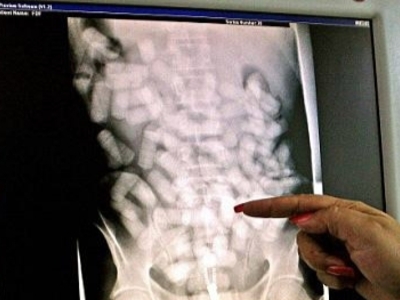

Man Dies While Trying to Smuggling Drugs

The man tried to smuggle drugs in his intestines. These were hidden in the condoms he swallowed. But one condom broke and killed the man almost instantly.